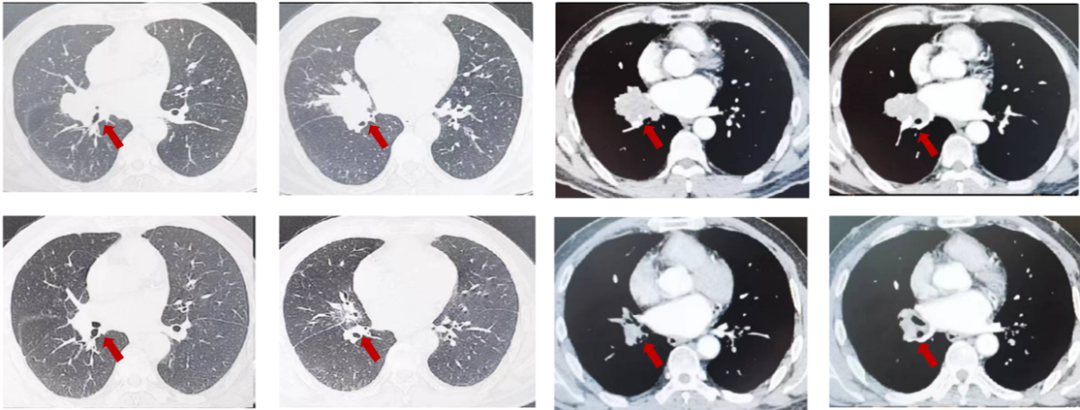

患者刘XX,男,65岁,2021年6月以“右胸痛2个月”为主诉入院,NRS7分,PS1分,吸烟30年,每天20支。外院胸部ct提示:右肺上叶团块影,PET/CT提示:右肺上叶前段可见不规则软组织肿块,范围约68mmx47mm,SUVmax=16.7,病变侵犯胸壁及右侧第4前肋;右肺上叶另见肿块及小结节,葡萄糖代谢增高。纵隔4R淋巴结代谢略增高,右肺上叶前段肺内转移;右肺门淋巴结代谢略增高,SUVmax=3.7,纵隔4R及右肺门淋巴结转移可能性大,未见胸膜增厚及胸腔积液,肝内钙化灶;气管镜取得病理,结合免疫组化为鳞状细胞癌,PD-L1(22C3)CPS=15。cT3N2M0 IIIB期,经MDT讨论后,为潜在可切除者先行免疫联合化疗,进行转化治疗,替雷利珠单抗+白蛋白紫杉醇/卡铂治疗3周期治疗,评效为缩小的SD。NRS 2分。

图1:由上至下分别展示基线(A.)及免疫化学治疗后改变(B.)。红色箭头指示病灶位置,由左至右分别为右肺肿物肺窗、右肺肿物纵隔窗、肋骨三维重建。